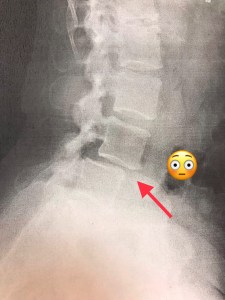

Successful surgery!